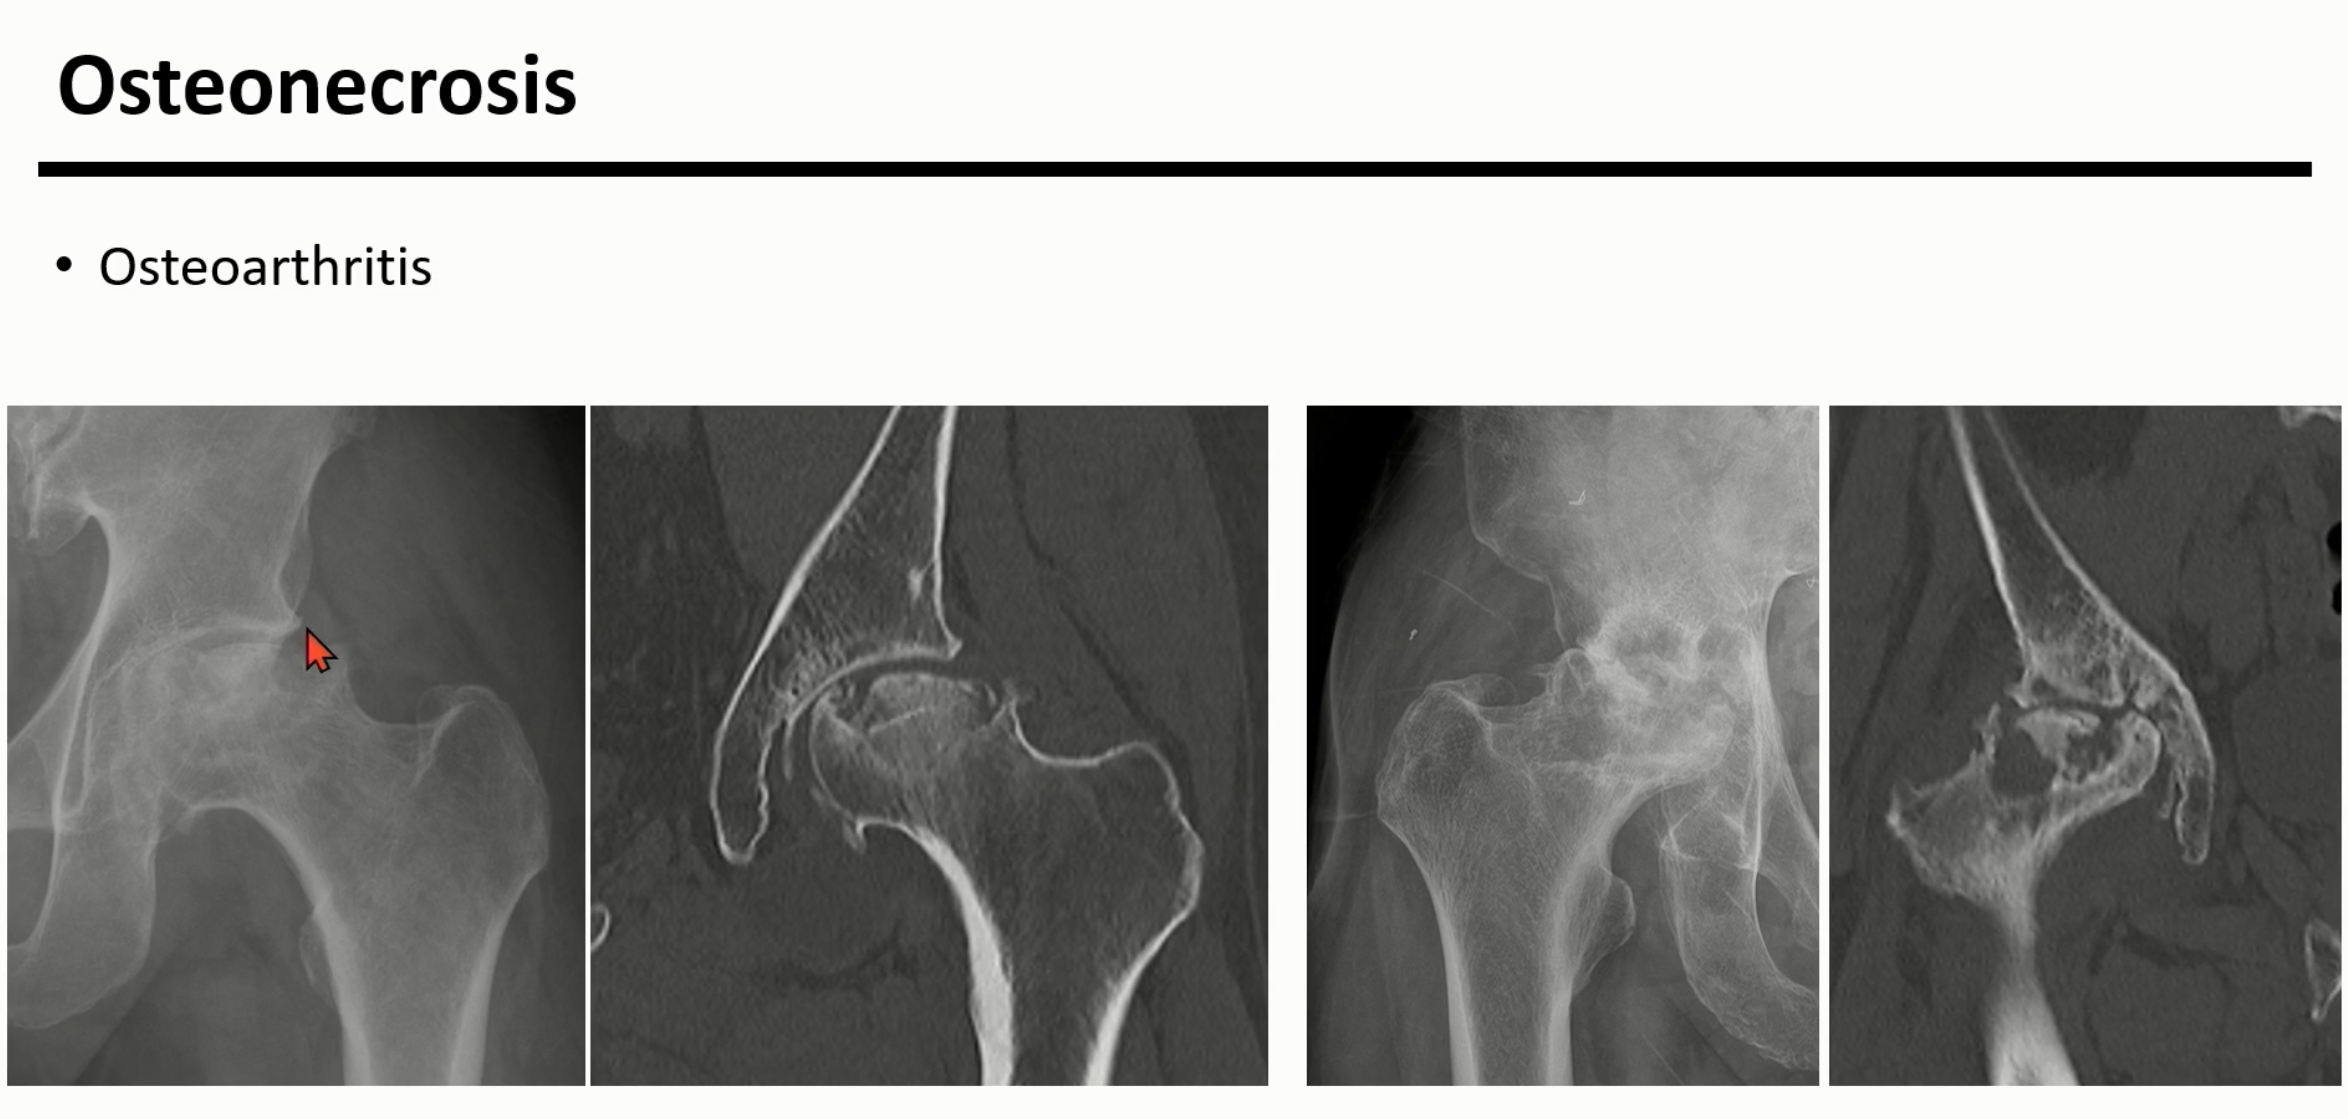

더 진행되면 crescent sign이 더 아래로 진행되고, collapse가 일어나면 femoral head의 flattening으로 진행됩니다.

femoral head의 flattening으로 진행되면 결과적으로 2차성 골관절염으로 진행되게 됩니다.